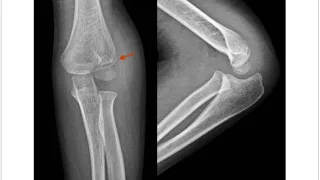

手術日+728日目 2026/2/25(水)(筋肉内神経鞘腫)